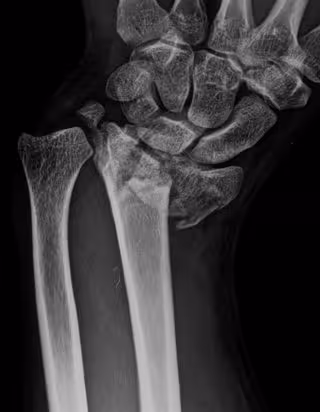

Fractura de radio

HOSPITAL LA LUZ - Archivo